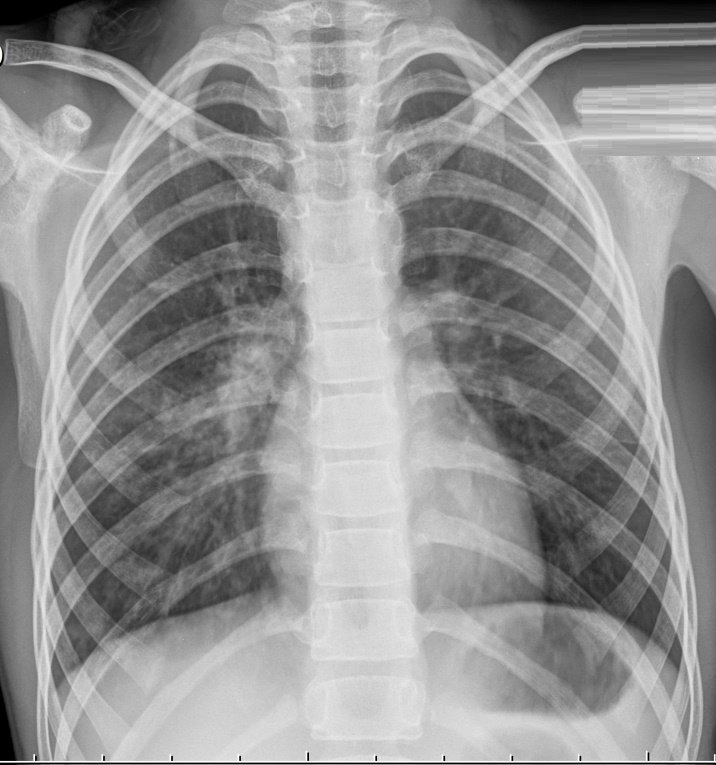

Пневмония на детских рентген-снимках

Пневмония на рентгенограмме у пациентов детского возраста не имеет выраженных отличий от взрослых, патология также характеризуется очагами просветления и затемнения. У детей в воспалительный процесс вовлекаются нижние отделы лёгких.

Рентгенография показывает следующее:

• очаговые затемнения диаметром 1-2 мм;

• увеличение внутригрудных лимфоузлов;

• деформация и усиление лёгочно-сосудистого рисунка;

• повышенная плотность затемнения (запущенная патология);

• в области патологического очага изменяется структура и размер лёгочного корня.

Как выглядит пневмония на снимке

Хоть общая картина детского рентгена не различается от взрослого, некоторая разница имеется. Первое — повышенная реактивность функций иммунной системы. Поэтому даже незначительный инфильтрат способен спровоцировать воспалительную реакцию на обеих долях лёгкого.

При постановке диагноза ребёнку можно ошибиться, что связано с небольшим объёмом лёгочной ткани и повышенным присутствием лёгочного рисунка.